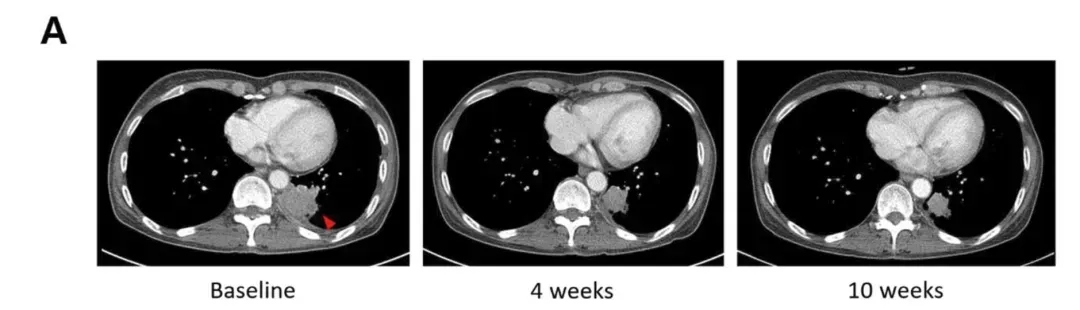

SNK01是美国NKGen公司开发的自体NK细胞疗法,抗癌活性更强,已证实对多种肺癌细胞系有杀伤作用!

《癌症免疫治疗杂志》公布其I/IIa期研究(NCT04872634)振奋数据:12例入组患者客观缓解率(ORR)25%,其中SNK01联合西妥昔单抗/吉西他滨/卡铂组ORR高达50%;疾病控制率(DCR)100%(3例部分缓解PR、9例病情稳定SD,详见下图C),中位无进展生存期(PFS)143天——联合西妥昔单抗组PFS145天(114–N/E天),联合吉西他滨/卡铂组143天(107–246天)。

▲图源“BMJ”,版权归原作者所有,如无意中侵犯了知识产权,请联系我们删除

更令人振奋的是,1例吉非替尼耐药的腺癌患者,接受该联合方案二线治疗后,影像学检查显示病灶显著缩小(详见下图A)!